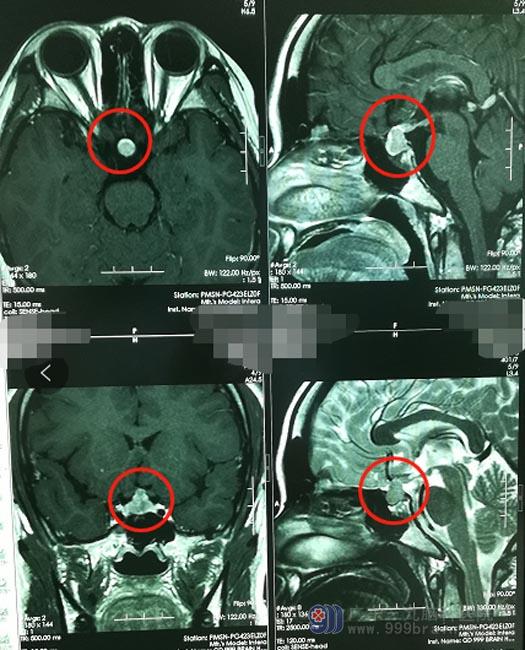

这一查,还真发现了问题:鞍区占位性病变,怀疑垂体瘤。为了解疾病真相,小陈听从亲戚的意见,来到了广东三九脑科医院外五科。入院后进一步头部MR检查,结果显示:鞍上及鞍内占位性病变,范围约1.0cm×1.3cm×1.2cm,内分泌检验结果显示垂体催乳素水平明显增高。

小陈具有明显的手术指征,家属也同意手术治疗,完善术前准备后,由医院副院长、神经外五科主任鲁明主刀“行鞍区占位切除术”,使用内镜经鼻蝶方式,术中磨除蝶窦前壁及鞍底骨质,纵行剪开垂体,可见肿瘤组织,位于鞍内及垂体柄除,质地韧,鱼肉状,术中冰冻病理考虑生殖细胞瘤,继续切除部分肿瘤送检。术后病理结果显示鞍区生殖细胞瘤。